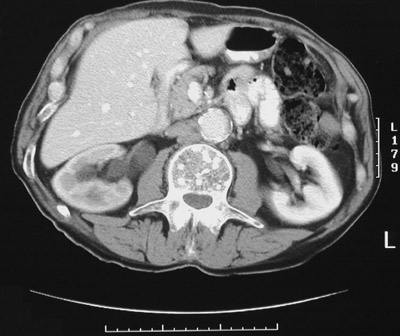

Image 3.8

This is a CT scan. What would account for the brightness of the lesions present in the vertebral body seen here?